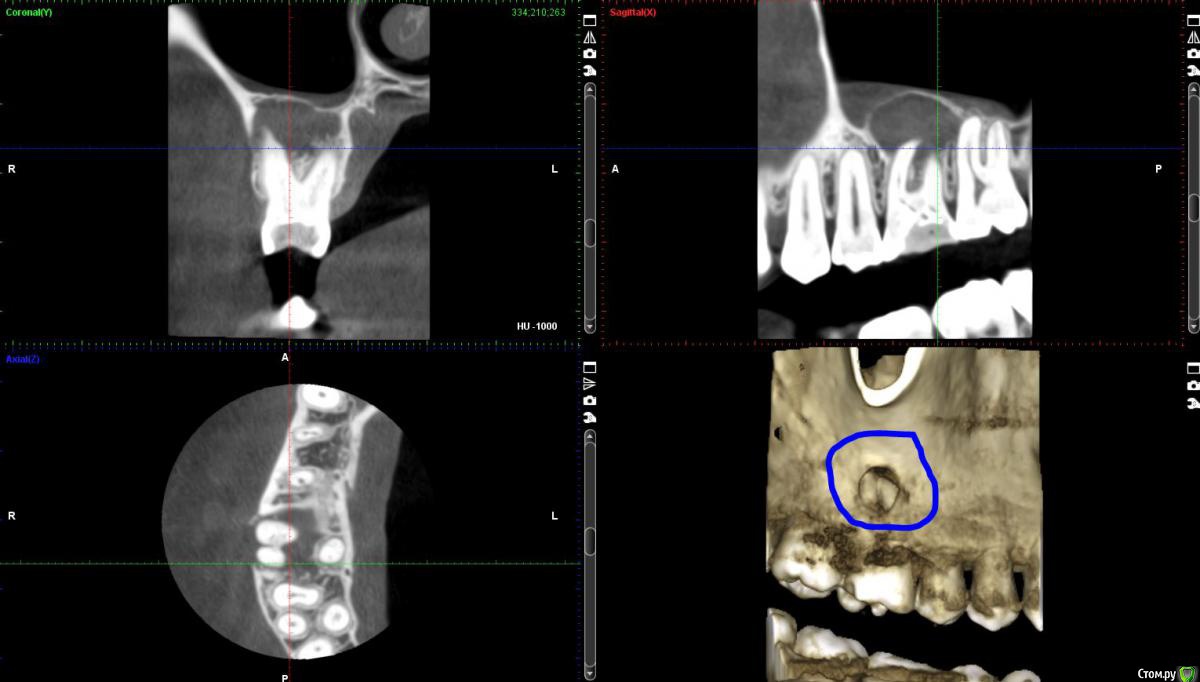

vchistyakov Опубликовано 13 декабря, 2017 Поделиться Опубликовано 13 декабря, 2017 Уважаемые специалисты! Спешу к вам за профессиональным мнением и советом. Хроника вопроса выглядит следующим образом: 1) Имеем зуб, шестёрка верхняя справа. Иногда тянущее ощущение почти у основания десны (обычно утром пока не поднялся). При нажатии на эту область двумя пальцами ощущения лёгкое болевое ощущение. В основании десны (где начинается верхняя губа) языком прощупывается комочкообразное уплотнение. 2) Ортопантомограмма сделана. В местах где делал, сказали, что есть подозрения на кисту. Фото в прикреплении. 3) Стоматолог-терапевт отправил на рентген отдельного зуба. Делали два раза, ничего не увидел. Посоветовал сделать КТ. 4) КТ сделано, стоматолог-терапевт снова в нём кисту не видит. Говорит, что корни влезли в пазуху и лучше зуб не трогать вообще, а кисты нет. Архив сейчас можно скачать по ссылке (https://drive.google.com/drive/folders/1P3iMeAWCg0PXtU2NDpLzwrDNNR52io5_?usp=sharing). Скриншот с КТ в трёх плоскостях прикрепляю вместе с сообщением. Своему стамотологу-терапевту доверяю как специалисту, т.к. хороший профессионал. В этом вопросе хочу узнать мнение как можно большего количества специалистов. Спасибо большое заранее. Ссылка на комментарий

АнтонТЛТ Опубликовано 13 декабря, 2017 Поделиться Опубликовано 13 декабря, 2017 Как кисту такого размера можно не увидеть... 2 Ссылка на комментарий

vchistyakov Опубликовано 13 декабря, 2017 Автор Поделиться Опубликовано 13 декабря, 2017 Как кисту такого размера можно не увидеть... :-( не знаю. То, что я сам увидел, меня очень расстроило. Но врач сказал, что самостоятельно результаты КТ смотреть не стоит. Значит киста очевидная? Какие дальнейшие шаги? Ссылка на комментарий

dok1 Опубликовано 13 декабря, 2017 Поделиться Опубликовано 13 декабря, 2017 Вскрыть зуб. Оценить его пригодность для лечения. Если стенки придесневой части, корней и дна полости целые - грамотное лечение каналов и восстановление в последующем наддесневой части зуба. И всё будет хорошо. 4 Ссылка на комментарий